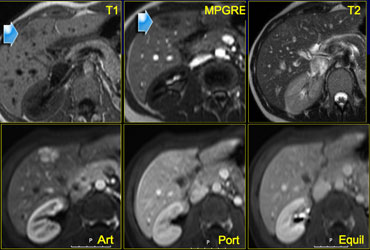

Small FNH Small FNH

Focal Nodular Hyperplasia (5)

On the left another FNH on MR.

The lesion is almost isointense to liver on T1WI and T2WI, but shows more contrast to the liver on a T1W-MPRGRE (gradient-echo).

The enhancement in the arterial phase is lobulated with nonenhancing septation and in the equilibrium phase the lesion is not different from normal liver parenchyma.

Notice that the lesion has a small scar.

Small FNHs often do not have a central scar on imaging and even not on pathologic examination.

Incidental hypervascular lesion on a CTA for pulmonary emboli Incidental hypervascular lesion on a CTA for pulmonary emboli

Focal Nodular Hyperplasia (6)

Another FNH on the left, in order to get really familiar with these common lesions.

On a CTA for pulmonary emboli a small hypervascular lesion is seen in the liver.

Further evaluation was done with MR.

On T1WI the lesion is not seen and on T2WI it is only slightly hyperintense.

In the arterial phase there is homogeneous enhancement and in the venous phase the lesion is not seen.

Provided that this patient does not have liver cirrhosis, this is probably a benign lesion, probably FNH.

As the appearance was not pathognomonic for FNH, a follow up examination was done and the lesion had not changed, making the diagnosis FNH most likely.